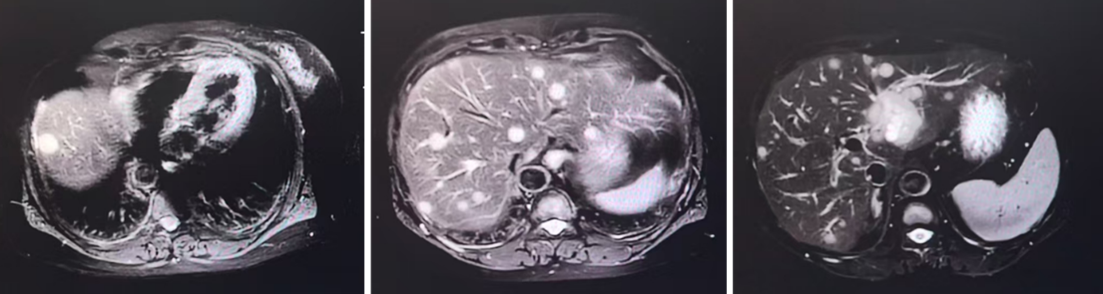

2025年8月,患者出现脑部多发转移(额叶、小脑及颅骨)。在完成颅内放疗后,基于其PIK3CA突变及扩增背景,考虑到患者基础情况较差,无法耐受化疗,且既往激素受体存在表达,参考INAVO120研究治疗模式,医疗团队果断采取联合靶向策略。

疗效评估: 治疗后复查影像学,患者肝脏病灶显著缩小,评效实现部分缓解。